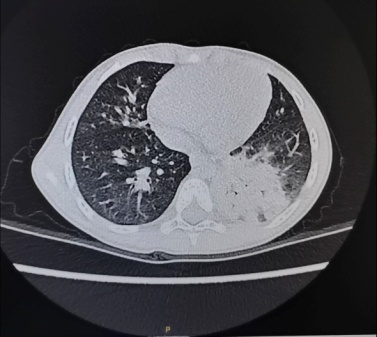

灌洗前肺CT 灌洗后肺CT 支气管镜下粘稠痰液

近日,北京儿童医院石景山诊疗中心(石景山医院儿科)为一名慕名而来的15岁重症肺炎患儿成功地完成了电子支气管镜灌洗介入治疗。患儿就诊时已发热、咳嗽1周左右,家长焦急万分,经过肺CT、病原学检查等相关检查后诊断为重症支原体肺炎。得知北京儿童医院石景山诊疗中心已开展电子支气管镜介入诊治技术后,当即来到儿科寻求进一步诊治。患儿入院后,立即实施灌洗术,术后当晚症状明显减轻,患儿感受舒适,术后第三天顺利出院,2周后复查肺CT显示原有病变完全吸收,患儿的父母亲自来到儿科病房对医护表示衷心地感谢,“孩子太幸运了,在家门口就享受到这么优质的医疗服务”。